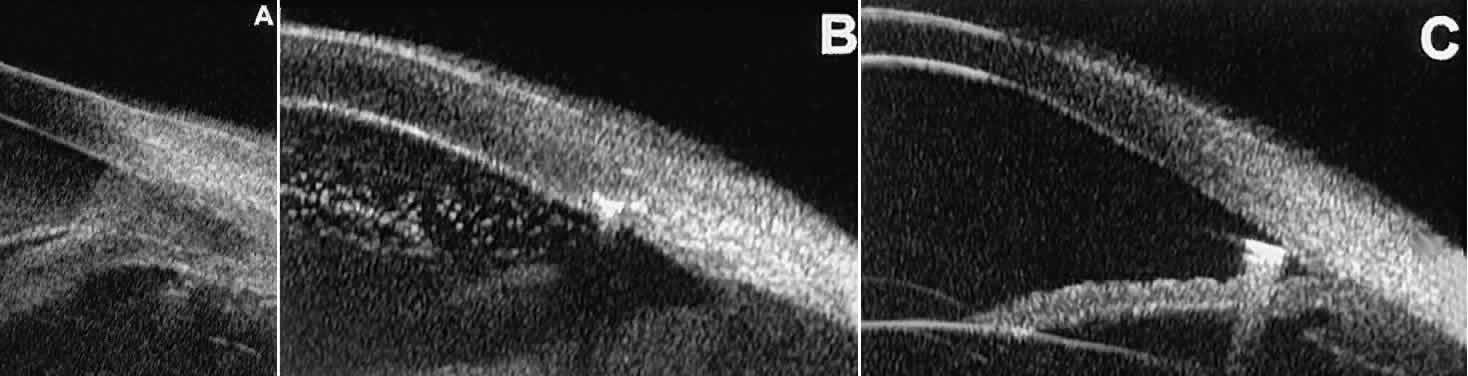

is hazy or opaque.  Fig. 9. Angle configuration in eyes with open-angle glaucoma. A. Wide open angle with flat iris plane (D40r configuration by Spaeth gonioscopic

grading system). B. Moderately wide angle with anteriorly bowed iris plane (C30r by Spaeth

gonioscopic grading system). Fig. 9. Angle configuration in eyes with open-angle glaucoma. A. Wide open angle with flat iris plane (D40r configuration by Spaeth gonioscopic

grading system). B. Moderately wide angle with anteriorly bowed iris plane (C30r by Spaeth

gonioscopic grading system).

Fig. 10. UBM features of special glaucoma cases. A. Pigment dispersion syndrome with posterior bowing of peripheral iris (“q” configuration by Spaeth gonioscopic grading system). B. Plateau iris syndrome with origin of iris from anterior surface of ciliary

processes behind peripheral iris, slitlike narrowing of peripheral

angle, and abrupt transition from steep peripheral iris to flat iris

midzone. C. Broad peripheral anterior synechia with posterior bowing of nonadherent

iris. D. Peripheral anterior synechia with aqueous-filled slit between site of

iridocorneal adhesion and iris root after cataract extraction with implantation

of posterior-chamber IOL. Fig. 10. UBM features of special glaucoma cases. A. Pigment dispersion syndrome with posterior bowing of peripheral iris (“q” configuration by Spaeth gonioscopic grading system). B. Plateau iris syndrome with origin of iris from anterior surface of ciliary

processes behind peripheral iris, slitlike narrowing of peripheral

angle, and abrupt transition from steep peripheral iris to flat iris

midzone. C. Broad peripheral anterior synechia with posterior bowing of nonadherent

iris. D. Peripheral anterior synechia with aqueous-filled slit between site of

iridocorneal adhesion and iris root after cataract extraction with implantation

of posterior-chamber IOL.